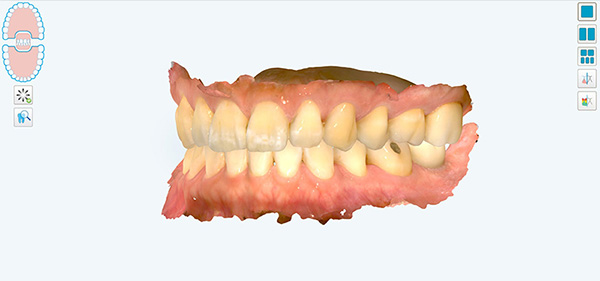

iTero Lumina 구강스캔

예전에는 치아의 배열과 교합을 알기 위하여 알지네이트라는 재료로 치아 본을 뜨는 과정이 있었는데요. 본을 뜨는 과정에서 알지네이트가 목구멍 쪽으로 넘어가거나 하면 헛구역질을 하는 경우도 있어서 환자분들도 많이 힘들어하셨습니다. 그러나 요즘은 구강스캐너로 카메라 사진 찍듯이 빠르게 스캔만 하면 되기 때문에 힘들게 치아 본을 뜨는 과정도 필요 없고, 치아 모형에 석고를 부어서 굳기까지 기다리는 시간도 필요 없게 되었습니다.

대치동 교정치과 연세정원치과에서는 iTero Lumina 라고 하는 가장 최신형의 구강스캐너로 구강 스캔을 진행하고 있습니다. iTero Lumina는 기존 스캐너에 비하여 스캐너 완드 사이즈가 작아지고, 카메라 갯수도 많아져서 더 빠르고 손쉽게 스캔이 가능해졌습니다 :)

이리저리 돌려보며 치아의 형태와 교합 상태를 직접 볼 수 있고, 교정 치료 후의 상태를 시뮬레이션하여 볼 수도 있습니다. 해상도도 매우 뛰어나서 충치나 치아 사이의 치석은 물론 치아 표면의 미세한 굴곡까지 선명하게 확인이 가능합니다.

구강스캔 연세정원치과